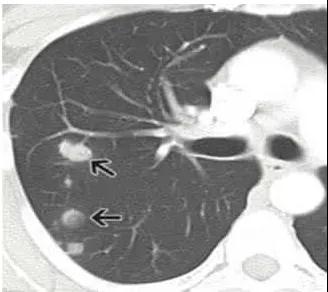

肺部結(jié)節(jié)是指在胸部影像學(xué)檢查中發(fā)現(xiàn)的直徑小于3厘米的球形病灶。肺部小結(jié)節(jié)是指直徑小于1厘米的球形病灶。

3、早期肺癌

比如錯構(gòu)瘤、血管瘤等良性的腫瘤,也可以表現(xiàn)為肺結(jié)節(jié)。

如果是體積小于1厘米的肺部結(jié)節(jié),通常都是良性的,而且這種結(jié)節(jié)體積太小,也沒有辦法進(jìn)行穿刺活檢。所以,對于這種大小的結(jié)節(jié),通常都是采取觀察,可以定期復(fù)查(根據(jù)情況,由醫(yī)生判斷,3個月、6個月或者一年復(fù)查一次),如果結(jié)節(jié)沒有長大或者體積變小,那么這個結(jié)節(jié)就多半是炎癥或者良性的腫瘤,那么就可以不用管它。如果長大了,尤其是迅速長大了,那么就要考慮手術(shù)切除。

如果體積大于1厘米,而且這個結(jié)節(jié)長得非常不好看——結(jié)節(jié)不規(guī)則,邊緣粗糙,有毛刺,那就是非常不好的信號,高度提示是肺癌。如果是這種情況,那么就要手術(shù)切除了。